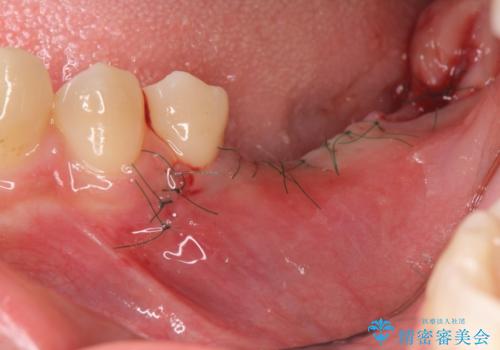

- 外科手術のため、術後に痛みや腫れ、違和感を伴います

- 外科手術のため、術後に出血、痛みや腫れ、違和感を伴います